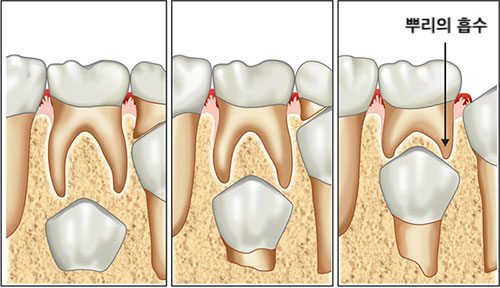

이 영구치 치배가 점점 자라나며 위로 올라오게 되는데 이때 위에 위치한 유치의 뿌리를 녹이면서 위로 올라오게 됩니다. 그래서 유치가 빠질 때 쯤 되면 유치가 흔들리게 되며, 유치를 빼고 난 이후 치아 모양을 보면 우리가 흔히 아는 치아 뿌리는 없고 치아 머리만 남아있게 되는 것이지요!

보통은 유치의 뿌리 밑에서 뿌리를 흡수시키면서 영구치가 올라오게 되는데 앞니가 나올 공간이 충분하지 않은 경우에는 유치의 뿌리를 흡수시키지 않은 상태로 안쪽으로 올라오기 때문에 유치는 흔들리지도 않는 상태에서 영구치아가 안쪽에서 나오게 되는 것입니다.

이렇게 안쪽에 위치한 유치라도 위의 두번째 사진 처럼 시간이 흐르며 혀의 힘에 의해 제자리로 위치하게 되므로 큰 걱정하지 않으셔도 됩니다.